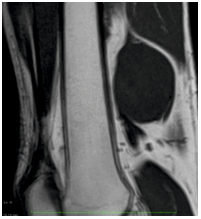

MRI scan (SIEMENS ESSENZA 1.5 TESLA) was done, which revealed a well circumscribed 5.6 x 4.3 x 5.3 cm mass in the posterior aspect of the left lower thigh appearing to be arising eccentrically from the sciatic nerve. T1 weighted images showed hypointense lesion (Figure 7) and T2 weighted images showed a hyperintense heterogenous lesion with a few cystic areas (Figure 6). Finally, the mass was confirmed to be a peripheral nerve sheath tumor, with the various imaging findings suggestive of schwannoma. The final diagnosis was peripheral nerve sheath tumor.

Figure 6: T2 weighted PD fat sat

Figure 7: T1 weighted – showing a hypointense lesion